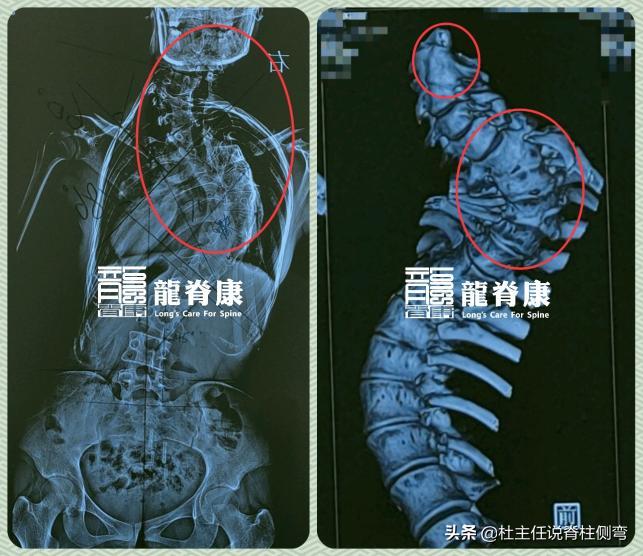

患者体表呈现出不对称、右背部隆起,剃刀背更是达到24°,臀部明显左移;其脊柱X线平片提示可疑 多个胸椎椎体畸形 。因此我们建议患者去做 颈椎、胸椎CT三维重建检查 ,明确颈胸椎椎体骨骼发育的情况,才能更好地帮助她制定治疗方案。

隔天,从外院颈椎、胸椎CT平扫+重建报告中我们得知,患者颈2/3及颈7-胸2椎体分节不良,胸7/8椎体半椎体或蝴蝶椎改变,所以我们判断,患者属于 先天性脊柱侧弯 !